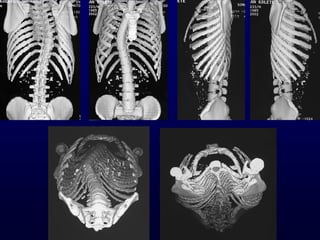

Πνμεγπεηνεηηθόξ έιεγπμξ

• MRI Οζθοαιγία, αοπεκαιγία

Κεονμιμγηθό έιιεημμα

Ηαηώηενμ (ΑΡ) θύνηςμα

< 10 εηώκ